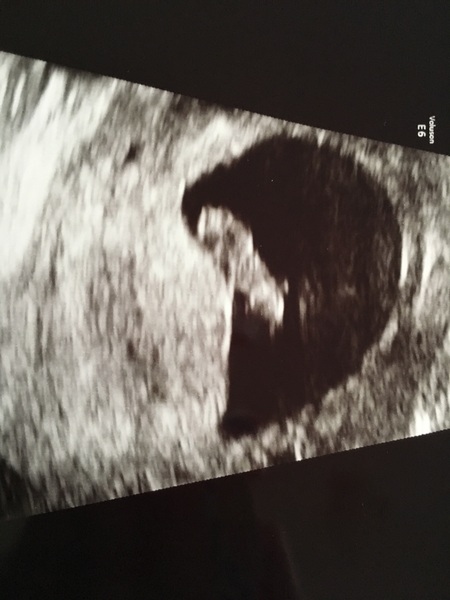

Just home for my scan and saw a heartbeat flickering away. Measuring 8+2, so only 4 days behind where I thought i was. Must've got pregnant the first time we dtd just a week after mva! So relieved and now just need to get through the next couple of weeks with no more bleeding. Sonographer couldn't see any reason for my bleed so we're thinking it is just dtd and old blood. Not too worried about it but will give it a rest until the 12 week scan at least..

Our little blobs look very similar haha!